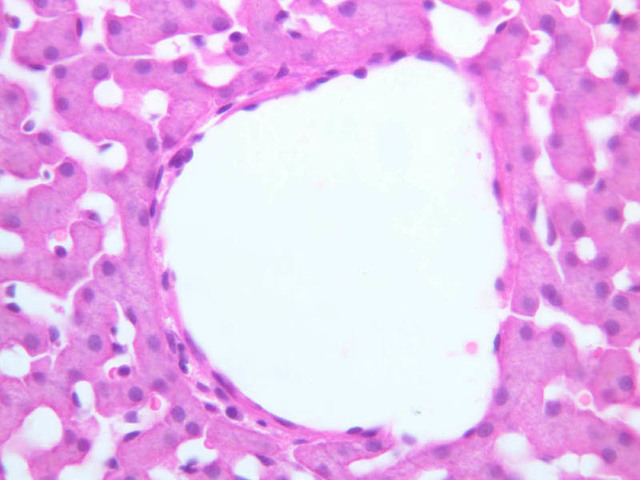

Now turn your attention to the system of pancreatic ducts. As you look for duct elements, bear in mind that the nuclei of duct cells tend to stain more lightly and to have less prominent nucleoli than do those of acinar cells. Begin by studying a number of different acini until you have identified several examples of centroacinar cells, which represent the initial segment of the duct system. Centroacinar cells are usually evident as lightly stained nuclei that lie, individually or in clusters of two or three, near the center of an acinus. Now look along the boundaries between acini for intercalated ducts (B-36, H&E [10x, 20x, 40x-labeled] [10x, 20x, 40x]), which appear in longitudinal section as trains of elongate, lightly stained nuclei and in transverse section as closely spaced, lightly stained nuclei surrounding a small lumen. Intercalated ducts drain into intralobular ducts, which are distinguished by their larger diameter. It is best to use the 10X objective as you begin your search for intralobular ducts (B-36, H&E [10x, 20x, 40x-labeled] [10x, 20x, 40x]). You want to be on the lookout for arrays of closely spaced nuclei surrounding a lumen. Conclude your study of the duct system by examining the connective tissue between pancreatic lobules for interlobular ducts, which may vary in caliber and epithelial lining (B-36, H&E [10x-labeled, 20x, 40x]).

Using the 10X (B-29, B-30)and 40X (B-29) objectives, examine several portal triads, noting the variable number of profiles of hepatic artery, portal vein and bile duct that comprise the portal triad. Near the boundary between adjacent lobules, try to find some of the small elements of the bile duct system known as canals of Hering.

Using the high dry objective, study the lining of the central vein and hepatic sinusoids (B-29). In some places the hepatocytes are exposed directly to the sinusoidal lumen, but, as a rule, there is a basal lamina which supports a discontinuous mosaic of endothelial cells and specialized phagocytic cells known as Kupffer cells. Find examples of Kupffer cells and endothelial cell nuclei. Note that in some places you may see a narrow space (the space of Disse) between hepatocytes and the basement membrane underlying endothelial and Kupffer cells. Using the oil immersion (100X) objective, look very carefully along the boundaries between adjacent hepatocytes to see if you can find a bile canaliculus--the most delicate portion of the bile duct system--the walls of which are formed by the plasma membranes of adjacent hepatocytes.